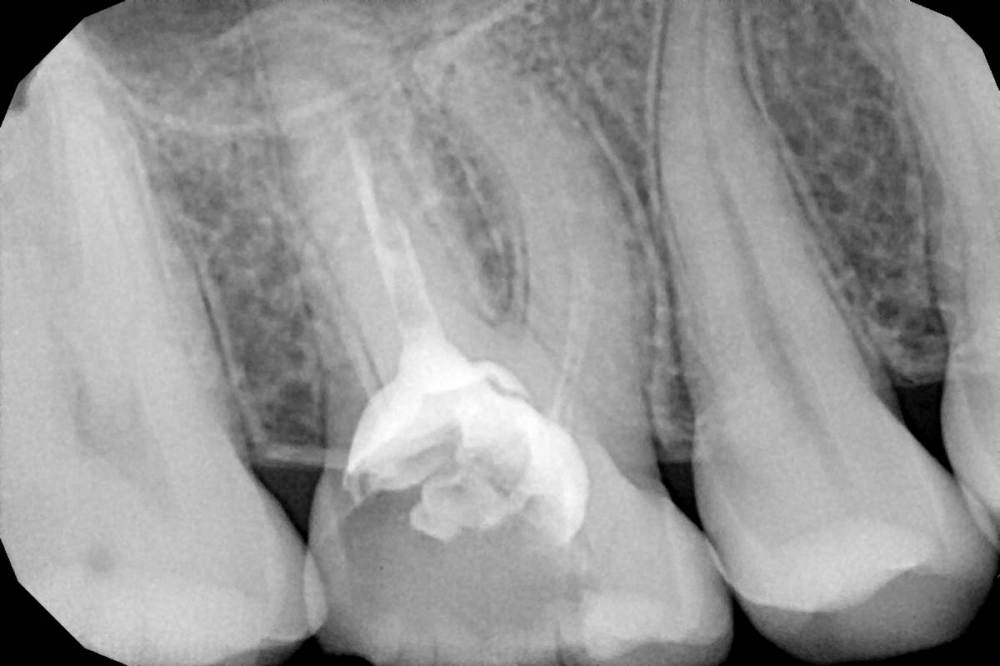

Женька Опубликовано 23 июня, 2021 Поделиться Опубликовано 23 июня, 2021 Коллеги, приветствую. Пришла пациентка с направлением на удаление 1.6-2.6 по ортодонтическим показаниям. Расспросив узнал, что принял решение такое ортодонт, тк премоляры интактны, а вот 1.6 эндодонтически пролечен. 2.6 с пломбой. Вопрос, оправдан ли такой подход? Есть лишь реконструкция КТ. Зубы я конечно не удалил, тк о таком подходе слышу впервые. Связавшись с ортодонтом узнал, что нестандартное удаление... Что думаете? p/s мудрые почему-то пока не удаляем... Ссылка на комментарий